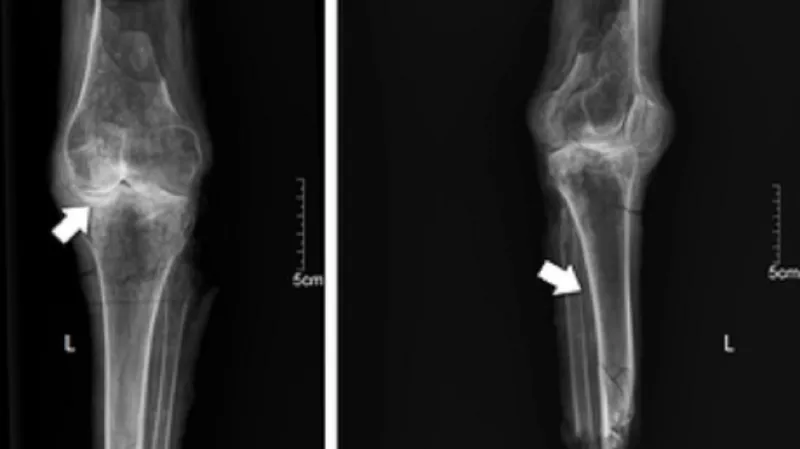

Rentgenové snímky potvrdily, že nohy patřily vysoké ženě

Vědci nohy podrobně prozkoumali pod rentgenem. Zjistili, že pocházejí ze stejného těla a patří osobě, která zemřela podobně jako Nefertari ve věku kolem 40 let. Vzhledem k tenkosti kostí usoudili, že šlo o vysoce postavenou osobu. Spočítali také, že ona osoba byla vyšší, než bylo v té době obvyklé. Urostlá byla podle dochovaných nástěnných maleb i Nefertari.